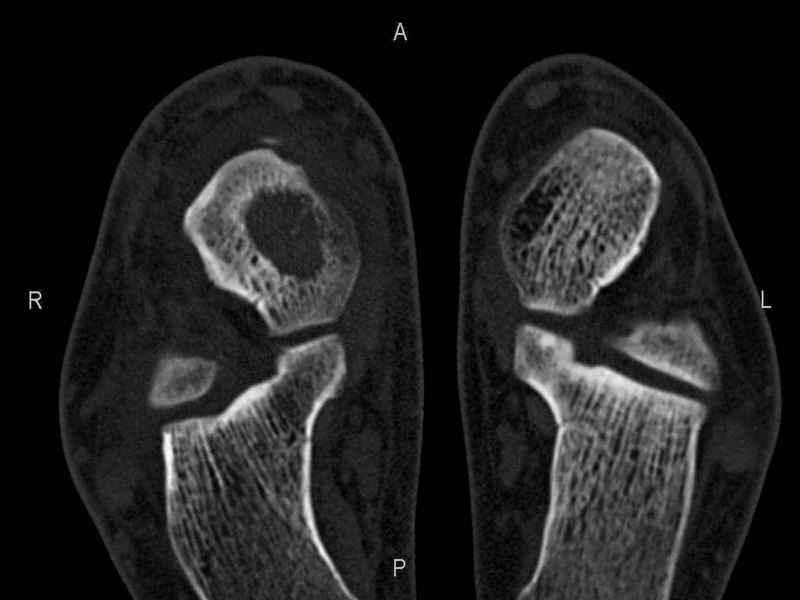

Рассекающий остеходрит + киста шейки тарана

Уважаемые коллеги, обратился за помощью пациент, мужчина, 25 лет. С жалобами на болевой синдром в области голеностопного сустава и среднем отделе стопы.

Травму отрицает. Со слов, болевой синдром в течении 1 года. Последние 1-1.5 мес периодически вынужден пользоваться костылями. После ограничения нагрузки боли уменьшаются. Соматически здоров. До появления болей активно занимался рукопашным боем.

На СКТ картина рассекающего остеохондрита блока таранной кости, киста шейки таранной кости с признаками импрессии суставной поверхности. А также - разрастания переднего края б\берцовой кости сопровождающиеся клиникой импиджмент синдрома.

Предполагаемый план лечения- удаление свободного фрагмента суставного хряща из трансмаллеолярного доступа с рассверливанием поверхности дефекта, кюретаж кисты шейки с заполнением полости биокомпозитом + дебридмент переднего отдела голеностопного сустава.